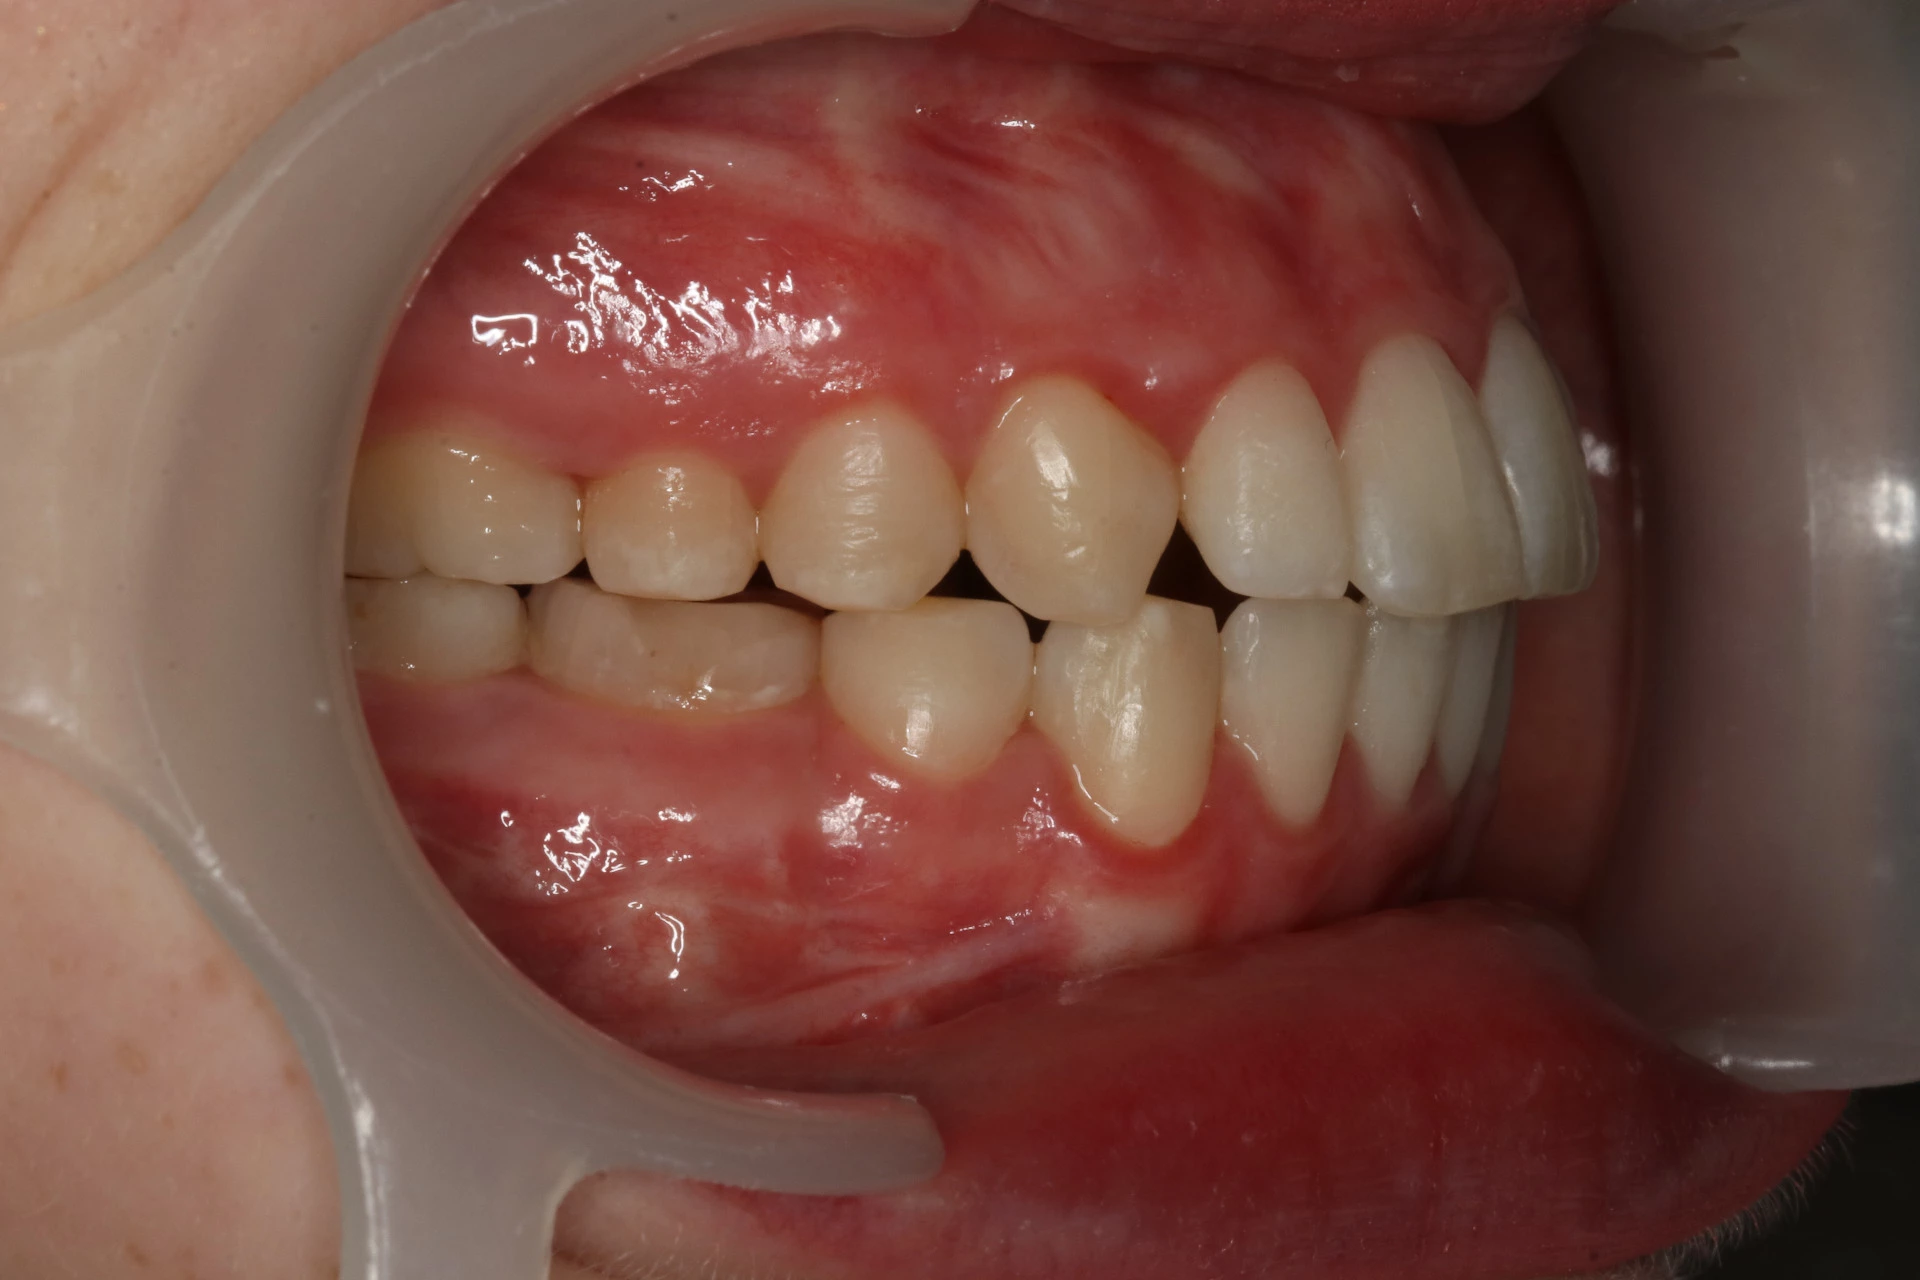

Vårt arbeid

Alle pasienter som vises har gitt skriftlig samtykke til at bildene kan brukes på klinikkens nettside.